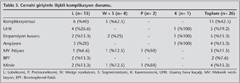

Operatif Mortalite, Postoperatif Komplikasyonlar ve Hastanede Yat?? S?resi

Postoperatif herhangi bir problemi olmayan olgu say?s? 11 (%42.3) idi. Bu olgular?n 6 (%75)'s? basit aspergillomal?, 5 (%27.7)'i kompleks aspergillomal? olgulard?. ?kisi (%25) basit, 13 (%72.2)'? kompleks aspergillomal? toplam 15 (%57.7) olguda? toplam 23 komplikasyon saptand?. Kompleks aspergillomal? olgularda istatistiksel olarak daha fazla komplikasyon geli?ti?i g?r?ld? (p=? 0.03). En s?k saptanan komplikasyonlar uzam?? hava ka?a??, ekspansiyon kusuru ve ampiyemdi (Tablo 3). Ampiyemi mevcut olan olgulardan birinde ve de uzam?? hava ka?a?? izlenen olgulardan birinde bronkoplevral fist?l saptand?. Bu iki olgudan birinde drenaj ve takip ile bronkoplevral fist?lde gerileme oldu, ent?be edilen di?er olgu postoperatif 20. g?nde eksitus oldu. Bu olgu cerrahi mortalite olarak kay?tlara ge?ti (%3.8). Mekanik ventilasyon ihtiyac? olan ?? olgudan biri mortal seyreden olguydu, di?er iki olgu postoperatif ent?be olarak yo?un bak?ma al?n?p 48. saatte ekst?be edilip sonras?nda ?ifa ile taburcu edildi. Olgular?n hastanede yat?? s?releri 12.9 ? 7 g?n idi. Bu s?re basit aspergilloma i?in 12.5 ? 7.5 g?n, kompleks aspergilloma i?in 13.1 ? 7 g?n idi. ?ki grup aras?nda istatistiksel fark yoktu (p> 0.05).